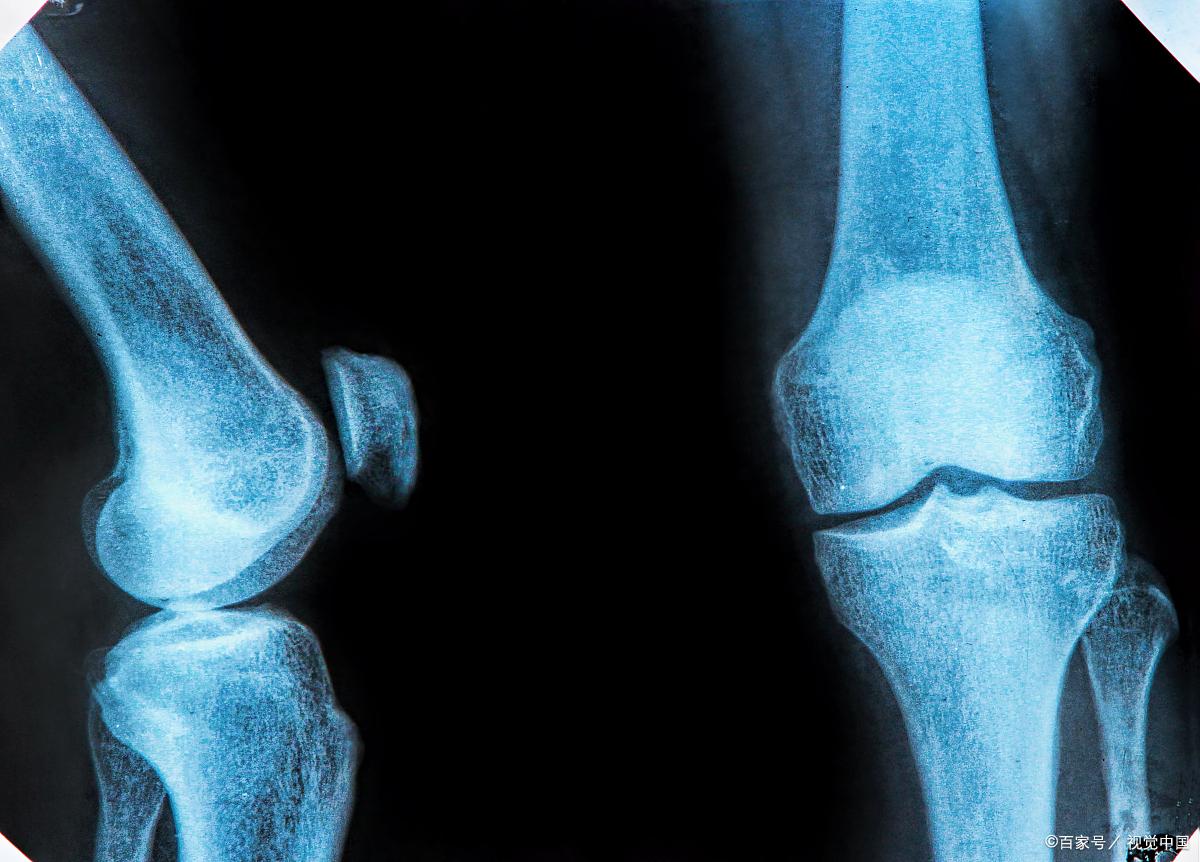

男孩比女孩晚长,在18-20岁左右停止发育,但一般20岁还在长的情况是比较少的,因为正常情况下,20岁的男生,骨骺线已经闭合了, 四肢骨骼和脊髓骨完全骨化,身高停止生长。